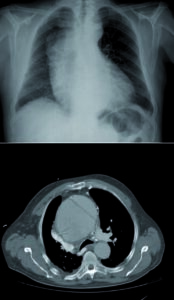

L’aneurisma dell’aorta toracica è una condizione medica caratterizzata da una dilatazione fusiforme o sacciforme del vaso, con un diametro che eccede di almeno il 50% rispetto a quello normale. Se l’aneurisma è voluminoso, può presentarsi all’RX torace come una massa mediastinica.

La Tomografia Computerizzata (TC) con mezzo di contrasto rappresenta il gold standard nella valutazione dei diametri dell’aneurisma. Questo metodo diagnostico fornisce una definizione ottimale del lume aortico e permette di identificare l’eventuale presenza di trombi e calcificazioni parietali.

La radiografia del torace nella dissezione aortica è spesso negativa ed aspecifica, ma può essere utile in caso di dolore toracico acuto per escludere cause alternative di dolore come pneumotorace, polmonite e versamento pleurico.

La diagnosi di dissezione aortica può essere effettuata attraverso la TC, che consente di evidenziare segni indiretti all’esame senza mezzo di contrasto come calcificazioni intimali dislocate, iperdensità del flap, ematoma intramurale iperdenso, emopericardio, emomediastino, emotorace (segni di rottura).

Dopo la somministrazione del mezzo di contrasto, la TC consente di evidenziare il segno diretto della dissezione rappresentato dal flap intimo-mediale. Questo appare come una sottile immagine ipodensa lineare o curvilinea nel contesto del lume aortico opacizzato che separa vero lume e falso lume.